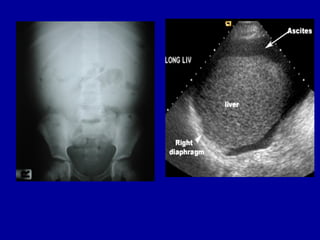

Imaging studies

• Chest and abdominal films

-elevation of diaphragm

-nonspecific signs

-hellmer sign

-obliteration of hepatic angle

-dogs ear/mickey mouse sign

-med displacement of cecum &

ascending colon & lat displacement of

properitoneal line

• USG

-site for paracentesis

-100ml fluid

-uncomplicated ascites

homogenous ,freely mobile, anechioc

collection in peritoneal cavity,deep

acoustic enhancement

-massive ascites

small bowel loops-polycyclic,lollypop

like arcuate app.